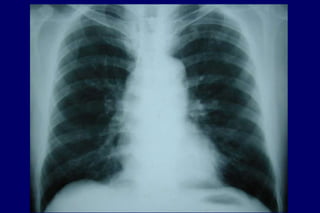

Radiografia

de tórax

Excluir outras

doenças

Bolhas

Hiperinsuflação

DIAGNÓSTICO História Exame físico Normal / quase Hiperinsuflação Murmúrio vesicular diminuído Sinaisde cor pulmonale mMRC-CAT Radiografia de tórax Excluir outras doenças Bolhas Hiperinsuflação Tabagismo Tosse Dispnéia Sibilos Exposição